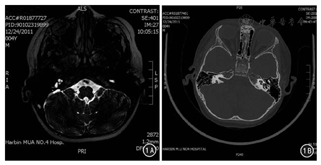

CT与MR内耳水成像各指标比较,MR内耳水成像诊断内耳各种畸形的灵敏度、特异度、准确度、阳性预测值和阴性预测值均高于CT,但差异均无统计学意义(P值均>0.05)。见表3、图1。

正常内耳MRI表现大致如下:内听道处于颞骨深处,于重T2WI上表现为椎管状高信号,直径大约在5 mm左右;内部脑脊液表现为高信号,可清楚观察到患者神经走行及与周围血管间关联[9]。半规管多为边缘光滑的C形结构,除椭圆囊处的半规管略微胀大外,其余部位较为均匀。耳蜗多呈高信号"蜗牛状"表现,球囊及椭圆囊结构可清晰呈现。而先天性内耳畸形、发育不全的患者于MR内耳水成像检测中多表现为影像缺失现象[10]。导水管综合征患者多表现为淋巴管、囊的扩张,于T2WI上内淋巴管多位于乙状窦的前方,表现为高信号,可于内耳的测量中显像,其中点宽度为0.1~1.4 mm,若其最大宽度超过1.5 mm则可诊断为淋巴囊扩张,该类型患者术中可出现搏动性脑脊液漏,严重者出现甚至出现井喷显像[11]。正常人体内听道于MRI中多为管、椎状高信号;血管、神经间隔、走行极为清晰;耳蜗形似蜗牛,球囊、椭圆囊较为完全,呈高信号;半规管表现为边缘光滑的C字形[12]。病理状态下MRI多表现为内耳Michel畸形、Mondini畸形等[13];前庭水管异常者多表现为淋巴囊异常增大,且呈高信号。相比螺旋CT,MR内耳水成像可更为精准地对耳蜗神经进行评价,对手术方案的制定意义重大[14]。